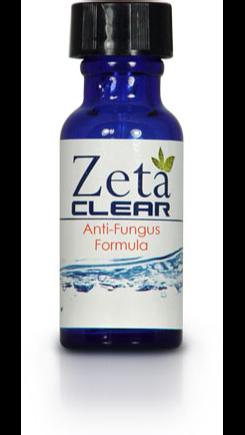

UnlockingthePowerofZetaclear's EssentialOilstoCureNailFungus

HealthBlogbusiness, RecoveryTactics,has publishedanewhow-toguide dedicatedtohelpingNail fungussufferersCureNail Fungus.

Thisguidewillalsohave informationusefultoanybody facingthechallengeof gettingridofNailFungus.

RecoveryTacticsstatesthat thisaccessible,easytofollow guideprovidesallofthe informationnecessarytofully understandthetopic.

TheFullHow-ToGuide Covers:UnderstandingNail Fungus-WhatisNail Fungusandhowisit treated?

Fact:Nailfungusisa persistentinfectionthat rarelyclearsupwithout propertreatment

Fact:Whilesomenatural remediesmayhavelimited efficacy,somestandoutasa provensolutionbackedby scientificresearch.